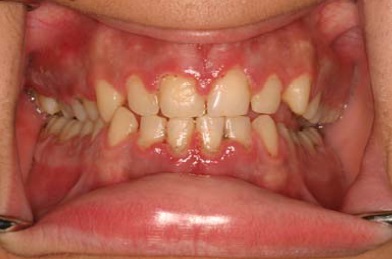

علت تورم لثه دندان یا باد كردن لثه دندان که ممکن است به صورت موضعی و یا کلی باشد میتواند عوامل مختلفی باشد. یکی از دلایل بروز انواع ورم لثه واکنش التهابی است که در پاسخ به تجمع ذرات غذا و باکتری (پلاک) در دندان ها اتفاق می افتد. این وضعیت در نتیجه عدم رعایت بهداشت موثر است و ممکن است منجر به بروز عفونت لثه شود و باید آنتی بیوتیک برای عفونت لثه و دندان مصرف شود. در شکل زیر یک نمونه از ورم کردن لثه به دلیل التهاب را مشاهده میکنید.

لثه ای که به این علت متورم شده است، اغلب نرم، قرمز و حساس به لمس بوده و به راحتی خونریزی میکند. خوشبختانه التهاب لثه را میتوان با رعایت بهداشت (مسواک زدن و نخ دندان کشیدن منظم) و پاک کردن جرم و پلاک و در نتیجه از بین رفتن مواد محرک در دندان، برطرف نمود.